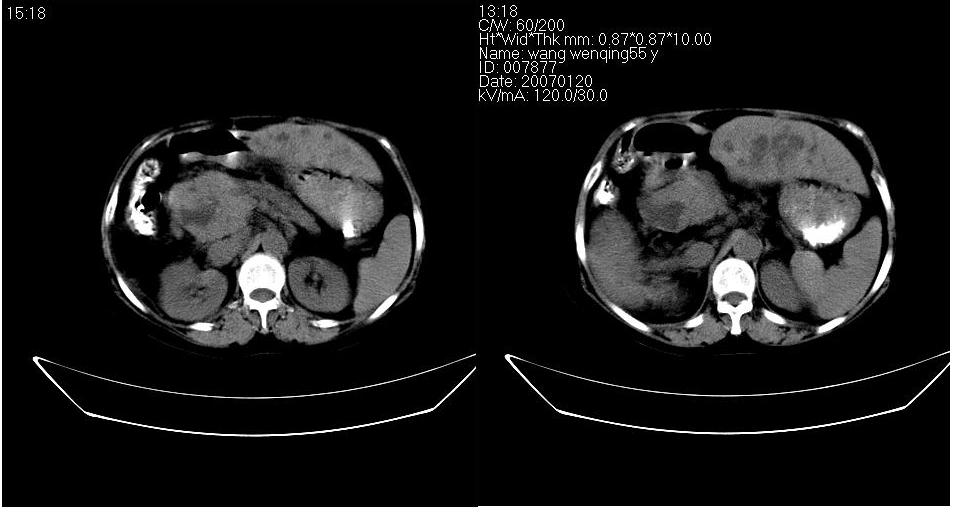

以下是引用守望可可西里在2007-1-20 23:09:00的发言:[br][br] 胰头癌,胆总管梗阻、截断,肝内外胆管重度扩张,肝内边缘部分的圆形低密度病灶多能与扩张的胆管较为连续,暂不考虑转移。病人没有黄疸吗?

以下是引用天南地北在2007-1-20 23:22:00的发言:[br]1:按照肿块的位置及胆总管的形态:考虑胆总管(中下段)癌并肝内胆管扩张,累及胰头。2:不排除胰头癌并肝内胆管扩张。[br]肝内病灶看起来还是扩张的胆管,不考虑转移先。